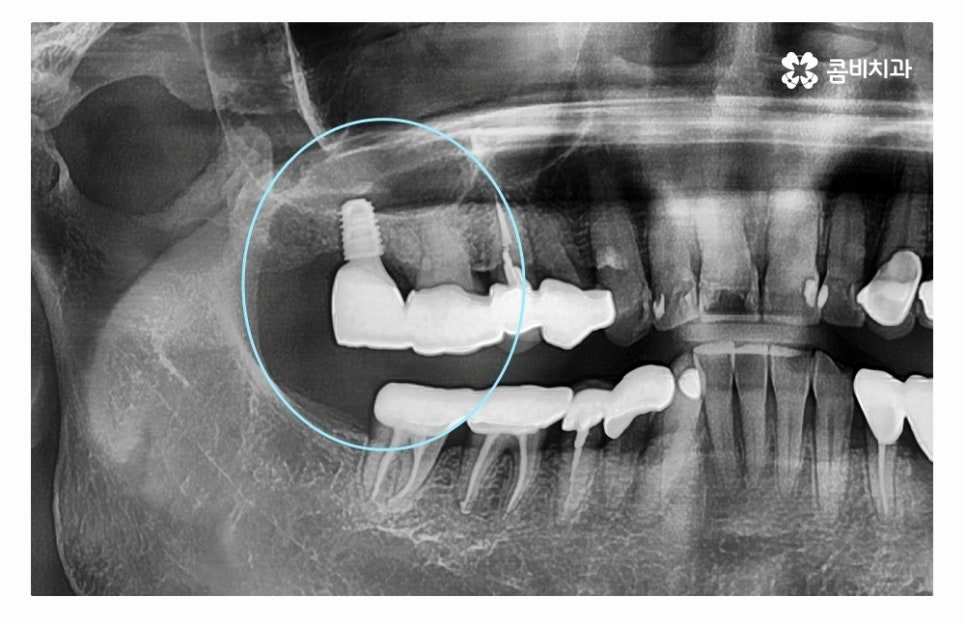

오늘 소개드릴 사례의 경우 충치로 인해 치아를 잃게 되었으며

발치 후 임플란트 수술을 통해 치아의 기능을 수복하였는데

치아를 잃게 되었을 때 원인을 잘 찾고 반복된 문제가 발생하지

않도록 정확한 진단이 필요하다고 할 수 있어요.

임플란트수술의 원리는 잇몸 뼈에 인공 치근을 식립하고

지대주로 단단하게 고정력을 얻은 후에 보철물을 연결하여

치료를 마무리하게 되는데 자연치아도 그렇듯이

임플란트 역시도 잇몸 뼈의 상태가 매우 중요하다고 할 수 있는데요.